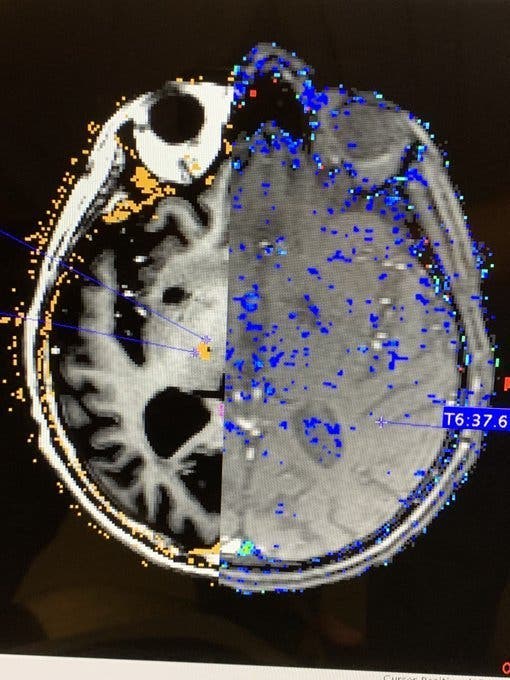

Pour ce faire, ils ont utilisé une sonde laser qu’ils ont pu introduire dans le cerveau, avec l’aide des images de l’IRM qu’ils visualisaient en même temps. Une opération portant le nom de « thalamotomie » comme l’explique le CHU Amiens-Picardie dans un communiqué de presse et qui, grâce à la maîtrise et la précision des experts, a été couronnée de succès. Pour expliquer ces résultats surprenants, Michel Lefranc, neurochirurgien et directeur de l’opération, a été interrogé par les journalistes d’Europe 1. « Dans un premier temps, on a descendu une petite fibre laser à l’aide d’un robot dans une zone très précise de son cerveau », a déclaré le médecin. Il précise également que la lésion a été brûlée et que « le tremblement ne reviendra plus ».